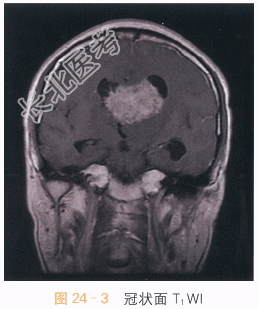

影像学资料如图24-1~图24-4所示。

读片分析:头颅MRI检查横断面T₂-Flair可见左侧侧脑室及透明隔区不规则软组织肿块,呈等高信号影,病灶内可见小片状囊变影,左侧侧脑室扩大,右侧侧脑室受压;增强扫描可见片状不均匀明显强化,囊变区无明显强化。结合患者病史,可考虑诊断为中央神经细胞瘤。